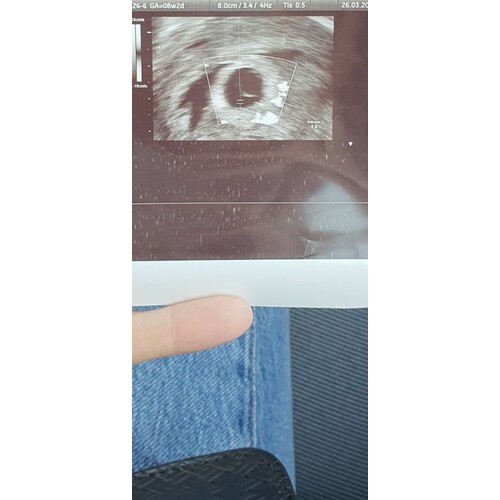

Niet gezien en ook niet gehoord. Vrucht is nog heel erg klein

Als je kijkt naar de echo.. lijkt de vrucht ook erg klein. :( ah ik weet t niet meer, nu weer afwachten tot dinsdag.

Bij weken moet je al het hartje zien kloppen op de echo of je cyclus is op hol dat je eigenlijk bijv nog maar in week 6 zit? Vaak doen ze ook nog inwendig om te checken..